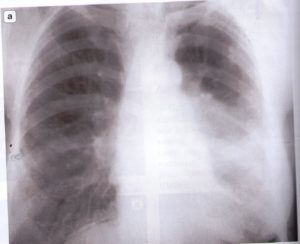

A nőknél a mediastinum érinti leggyakrabban. Ha az orvosok már gyanús egy nagyobb mértékben, a betegnek meg kell alávetni X-ray a szegycsont. Tedd ferde, és az oldalirányú vetülete mellkasát.